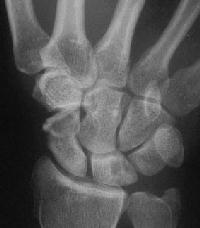

This progressed...

Click for larger image